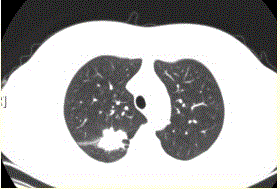

问题 患者女,54岁,无症状,常规体检透视时发现右上肺阴影。既往无结核病史。体格检查阴性。CT结果如下图。 局限性阻塞性肺气肿最常见的病因是

选项 A.支气管哮喘 B.支气管扩张 C.慢性支气管炎 D.大叶性肺炎 E.支气管肺癌 F.支气管囊肿

答案 E